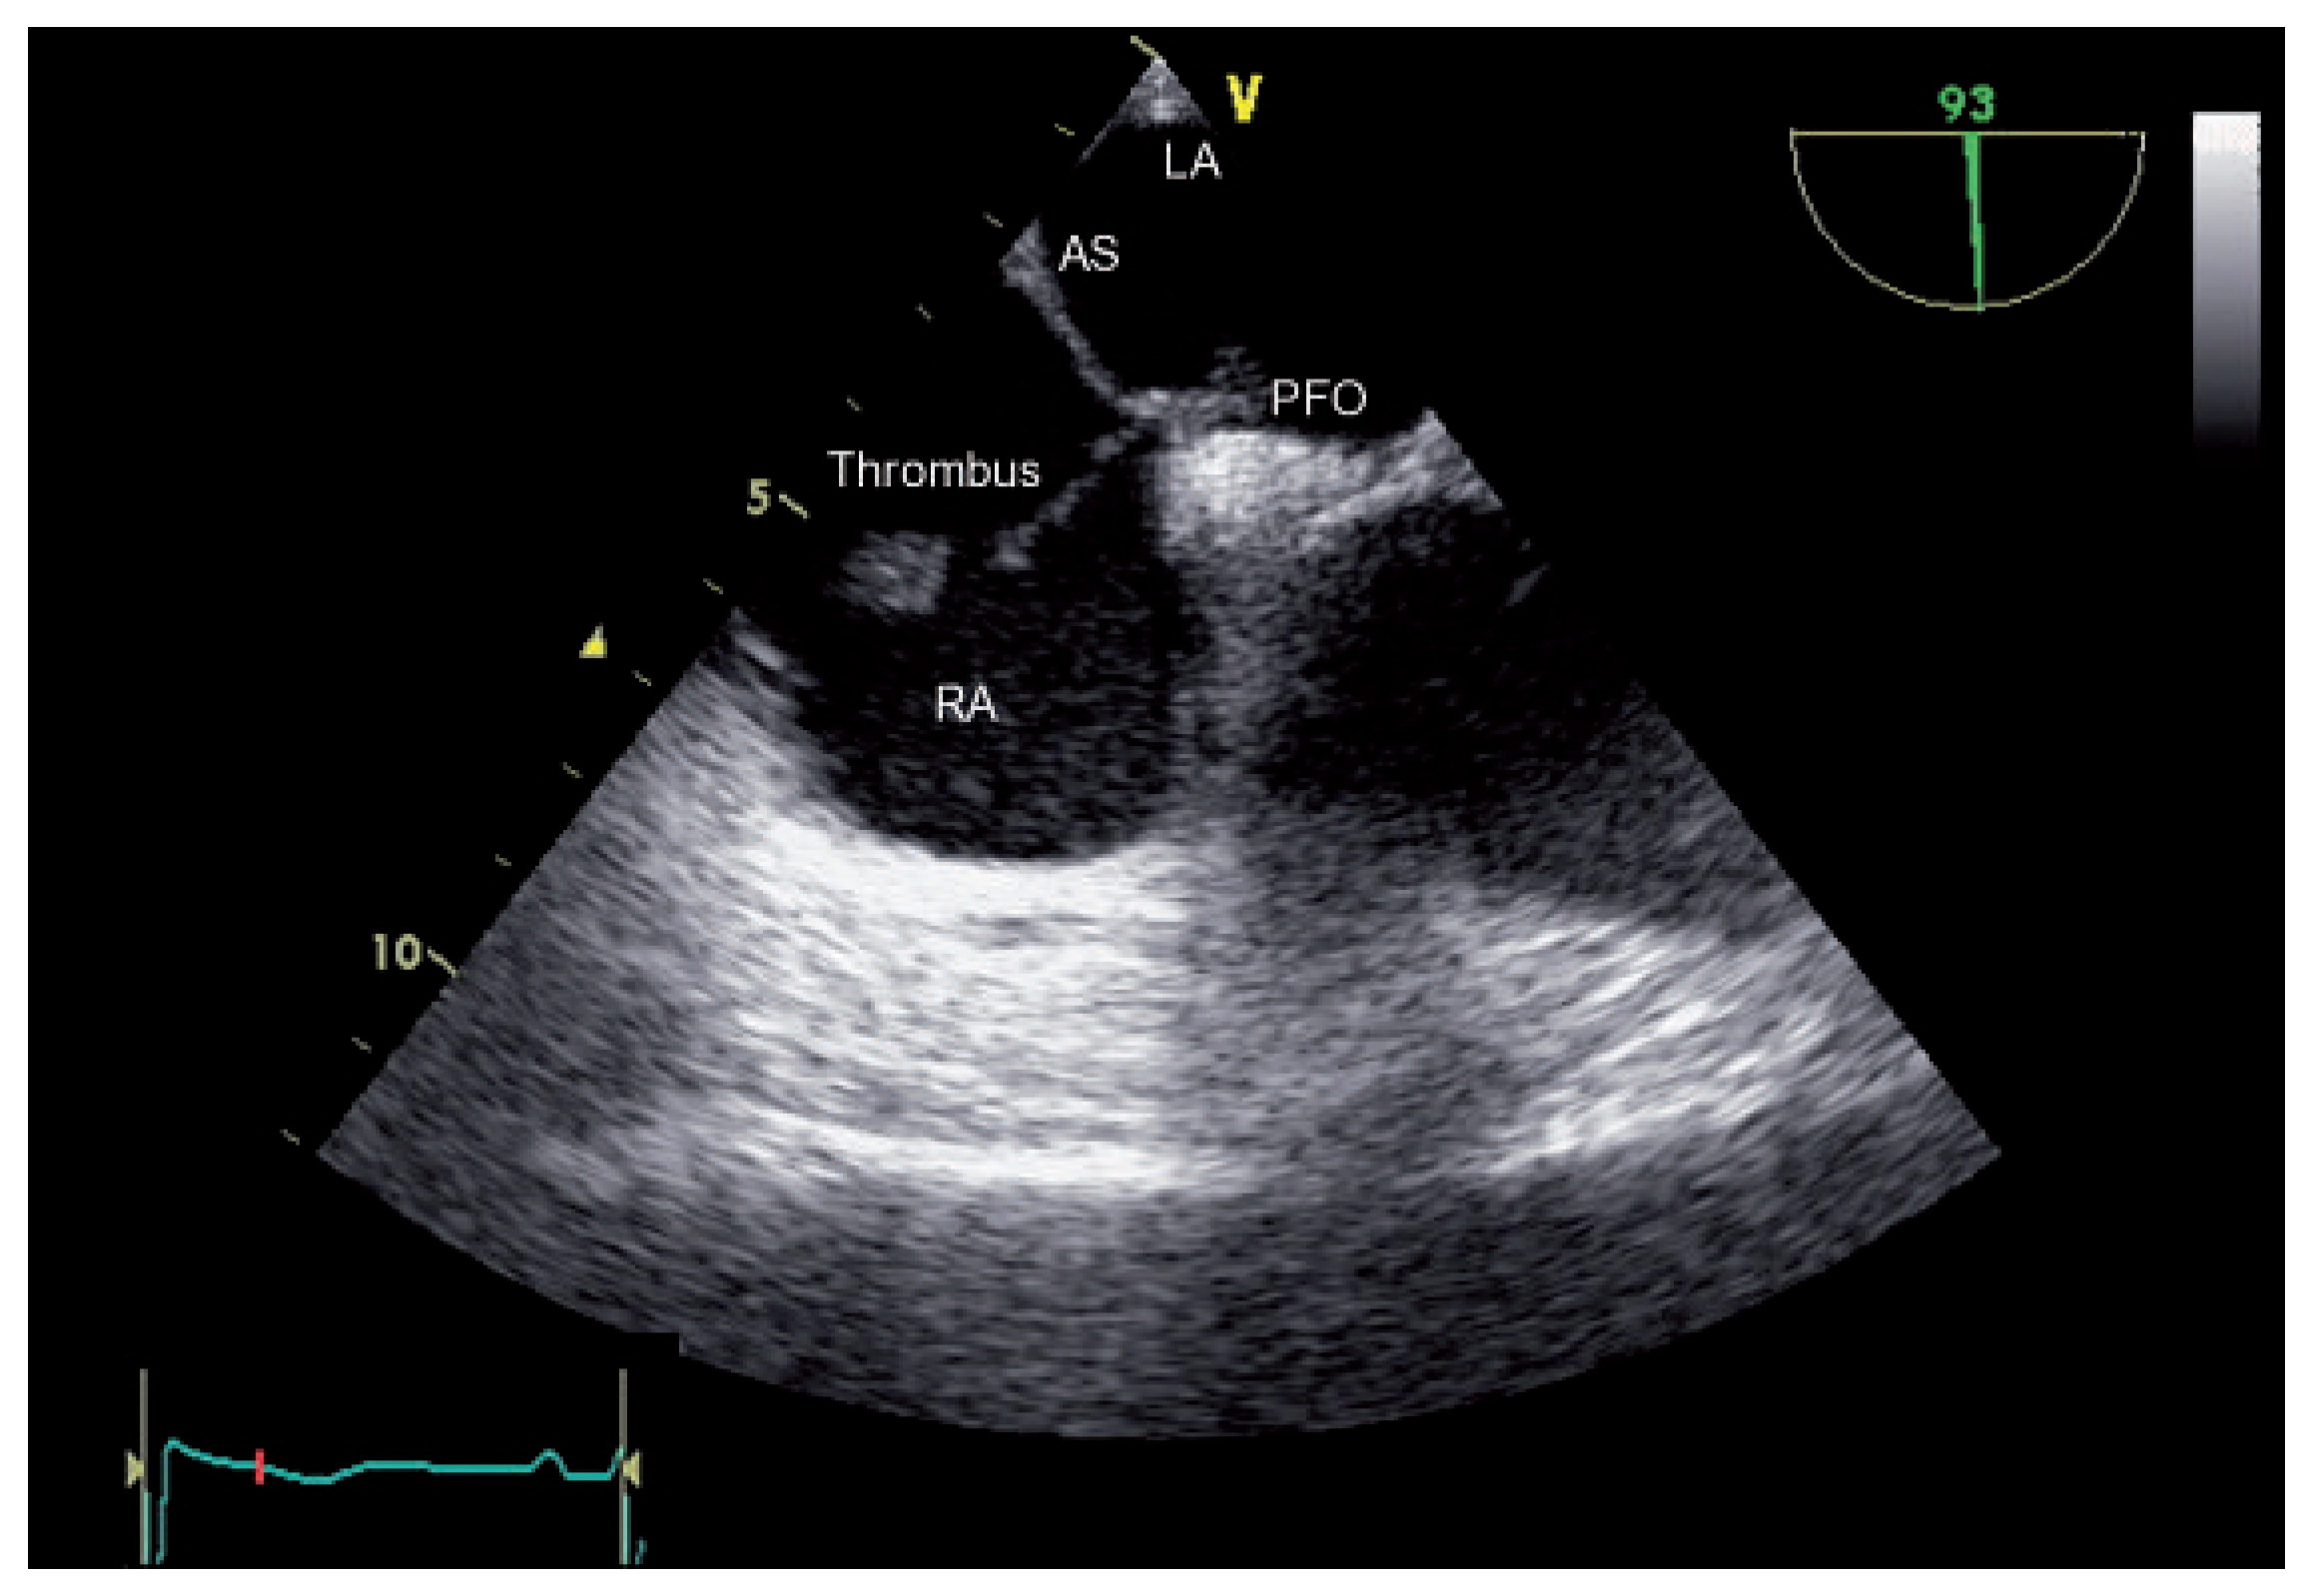

Trapped Thrombus in the Open Foramen Ovale